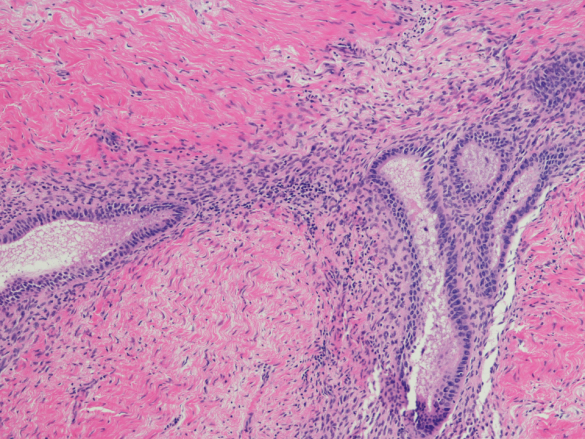

A endometriose é uma condição inflamatória crônica que acomete pessoas do sexo feminino, particularmente durante seu período reprodutivo, desde a adolescência (menarca) até a transição para a menopausa.

- Em resumo, o útero é revestido internamente por um tecido chamado de endométrio.

- Normalmente, a cada ciclo menstrual um novo endométrio é desenvolvido para receber um óvulo fertilizado. Quando isso não ocorre, ele é expelido. Ou seja, a menstruação consiste na eliminação periódica desses fragmentos.

- Em mulheres com a doença, os tecidos endometriais não são eliminados como deveriam.

- Assim, se esses tecidos não seguem o processo natural acabam caindo nos ovários, na cavidade abdominal ou ainda em outros órgãos, onde voltam a se multiplicar.

- Nesses casos, à medida que o ciclo menstrual segue seu ritmo, o acúmulo de tecido anormal fora do útero pode causar inflamações, sangramentos, cicatrizes e cistos, levando a uma série de sintomas e possíveis problemas.